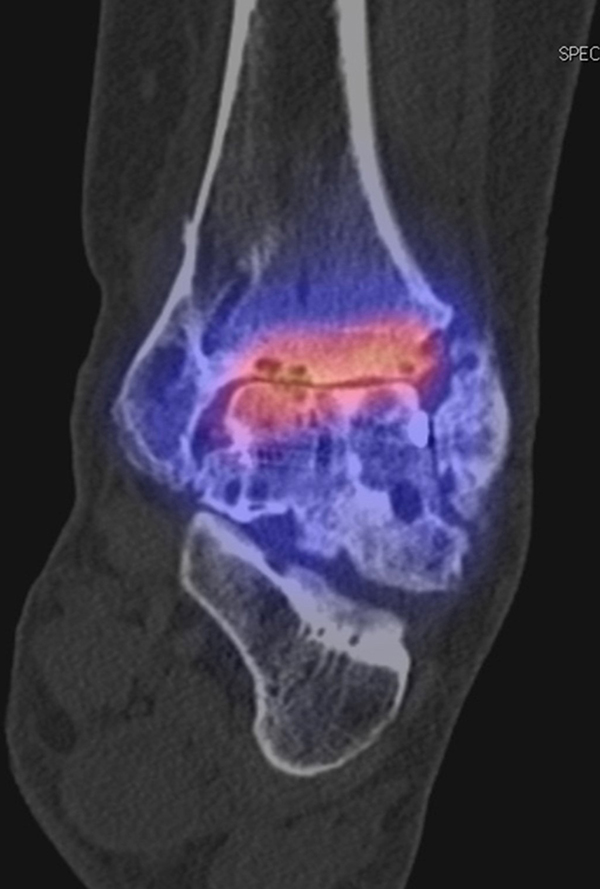

Beispiele für SPECT/CT-Untersuchungen nach OSG-TEP sind in den Abbildungen 6.1. bis 6.3. abgebildet.

Abbildung 1.2. zeigt eine ausgedehnte posttraumatische Arthrose im linken OSG. Der metabolische Focus liegt in der Hauptbelastungszone.